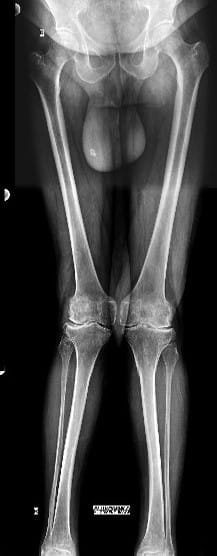

Your doctor will do clinical examination of knee joint, hip joint, spine and other joints of your body. X-rays of both knees will be performed. Occasionally, MRI of the Knee joint and few blood investigations may be required as per their underlying problem.